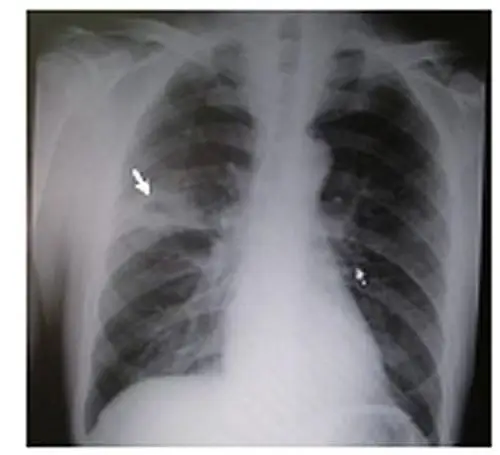

肺脓肿与普通肺炎相鉴别